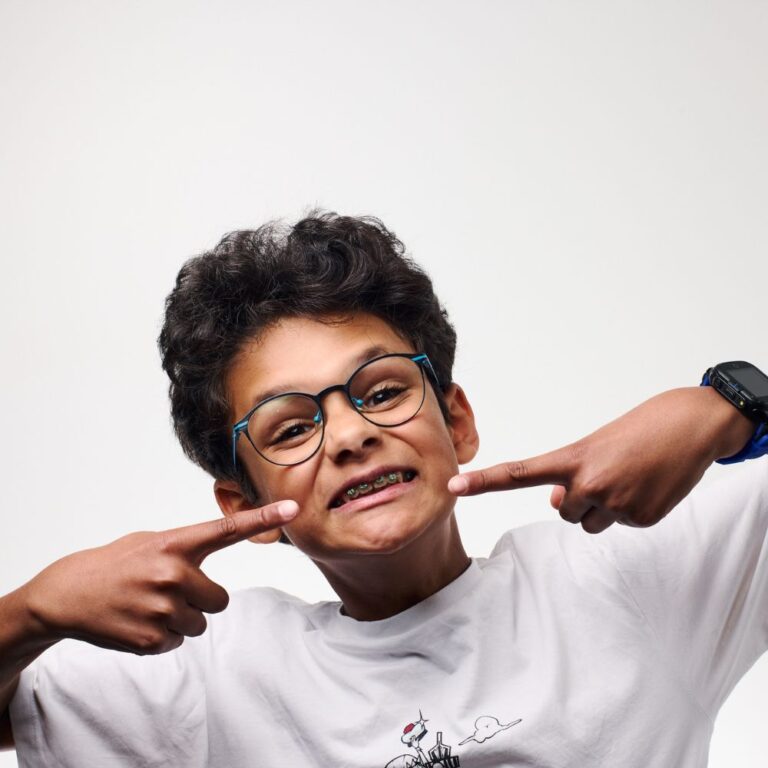

Dans notre cabinet, nous accordons une attention particulière au bruxisme chez les enfants, un phénomène qui, tout comme chez l’adulte, se manifeste par un serrage vigoureux des mâchoires ou par un grincement involontaire des dents.

Ces mouvements peuvent entraîner non seulement une usure des dents, mais aussi divers troubles musculaires et articulaires, touchant la tête, le cou et la posture. C’est pourquoi il est essentiel de les reconnaître rapidement et d’intervenir de manière précoce.

Le bruxisme peut apparaître dès la dentition temporaire et sa fréquence augmente vers l’âge de 6 ans. Environ 3 enfants sur 10 en sont concernés.

Dans de nombreux cas, le phénomène tend à diminuer spontanément avec la croissance. Cependant, lorsque le bruxisme est intense ou persistant, il est considéré comme une véritable dysfonction nécessitant une évaluation approfondie.

Le bruxisme est un signal indiquant qu’un processus physique ou émotionnel ne fonctionne pas de manière optimale. Comprendre son origine est essentiel, car il peut avoir des conséquences importantes sur la santé générale de l’enfant.

Dans notre démarche clinique, nous distinguons toujours avec précision le moment où l’enfant grince des dents.

Pendant la journée, on parle de bruxisme diurne ou d’éveil. Il est souvent associé à la tension, au stress ou à certaines habitudes comportementales.

Pendant le sommeil, forme la plus fréquente, le bruxisme peut être lié à la qualité du sommeil, à la respiration ou à d’autres facteurs physiologiques.

Cette distinction est essentielle pour proposer un parcours diagnostique et thérapeutique ciblé, adapté aux besoins spécifiques de chaque enfant et garantissant une prise en charge complète, multidisciplinaire et personnalisée.